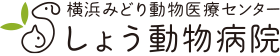

革新のcSound Quality

新概念のプラットフォーム

新ソフトウェア・ビームフォーマー”cSound”では、すべてのチャンネルデータを画像に活用し、ピクセル情報を演算処理することにより高画質を実現しています。